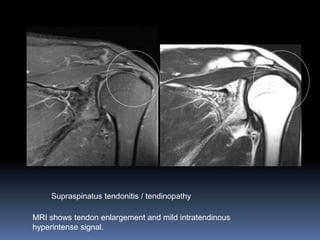

Supraspinatus tendonitis / tendinopathy

MRI shows tendon enlargement and mild intratendinous

hyperintense signal.